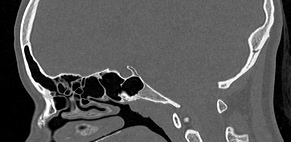

Основание черепа имеет сложное строение. Оно образовано лобными костями, решетчатой и клиновидной костью, височными и затылочными костями. На внутренней поверхности основания черепа лежат структуры ствола мозга, такие как средний мозг, Варолиев мост и продолговатый мозг, переходящий в спинной мозг на уровне большого затылочного отверстия. Поверхность основания черепа имеет многочисленные отверстия, через которые проходят черепно-мозговые нервы и сосуды головного мозга.

Наиболее информативным методом диагностики различных заболеваний в области основания черепа является мультиспиральная компьютерная томография. Исследование проводится с целью оценки травматических повреждений, диагностики аномалий развития костных структур, при планировании оперативных вмешательств, а также выявления воспалительных заболеваний и опухолевых процессов. Также на данном уровне может дифференцироваться аномалия Арнольда-Киари, заключающаяся в эктопии (то есть опущении) миндалин мозжечка различной степени выраженности.

В медицинских центрах «Доступная медицина» установлены новейшие мультиспиральные 64- и 128-срезовый компьютерные томографы экспертного уровня. В результате послойного сканирования с минимальным шагом от 0,5 мм получаются детальные изображения костных структур и прилегающих окружающих тканей. Благодаря инновационным возможностям аппаратов полученные при сканировании данные трансформируются в пространственные модели исследуемой области, которые можно увеличить, повернуть в разные стороны, рассмотреть все структуры в мельчайших подробностях. Новейшее оборудование позволяет проводить точную и достоверную диагностику заболеваний такой труднодоступной области как основание черепа. При этом современные аппараты оказывают минимальное лучевое воздействие на пациента.